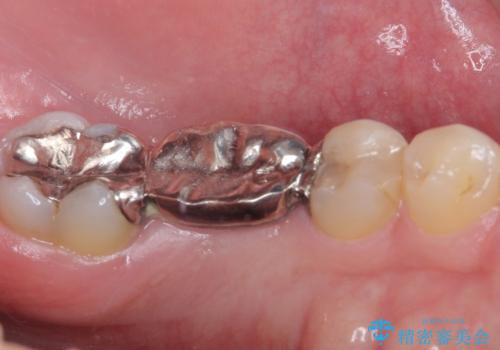

- 外れやすい銀歯をやり替えたいと来院された患者様です。

他院にて治療したインレーブリッジが何回か外れてつけ直しを繰り返しているため、外れないようにしてほしいとのことでした。

できるだけ外科処置は避けたいという患者様の希望と、すでにブリッジの土台となる両隣の歯を削って治療していることを考慮し、患者様と相談の上、今回はインプラントではなくフルジルコニアブリッジで治療することとしました。

より外れにくく精度の高いブリッジにするため、事前に親知らずの抜歯を当院で行いました。